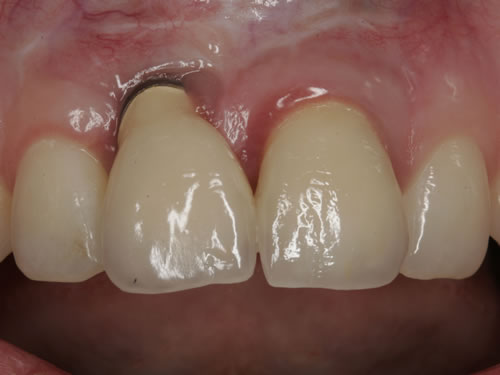

Häufig führt ein Zahnverlust zu einem Verlust von Knochen (Hartgewebe) und der bedeckenden Schleimhaut (Weichgewebe). Besonders im sichtbaren ästhetisch sensiblen Bereich ist es aber notwendig, dass sowohl Hart- als auch Weichgewebe so wiederhergestellt wird, dass im Idealfall das Zahnimplantat mit seiner Krone dem Aussehen des ehemaligen gesunden Zahn entspricht. Als Erfolgskriterien werden aus zahntechnischer Sicht die Form, Farbe und Größe der individuellen Krone angesehen. Aus medizinischer Sicht gibt es wichtige Erfolgskriterien, die die Implantatposition, die Implantatlänge, den Implantatdurchmesser, den Zahnfleischrand im Vergleich zum Nachbarzahn und die Zahnfleischpapillen zwischen den Zähnen beinhalten. Zusätzlich braucht man ein zahntechnisches Labor, das mit der Keramikverarbeitung ein natürliches Aussehen gestalten kann. Nur, wenn alle Parameter perfekt sind, ist das Ergebnis perfekt. Das macht den Einzelzahnersatz im Oberkieferfrontzahngebiet zu einer echten Herausforderung.

Nach der Entfernung von Zähnen kommt es schnell zu Knochenverlust (Resorptionen) und entsprechendem Verlust von Schleimhaut. Die Schleimhaut kann durch bestimmte Operationstechniken wiederhergestellt werden, in dem man freie oder gestielte Bindegewebstransplantate z. B. vom Gaumen entnimmt und das fehlende Material so ersetzt. Das Weichgewebe kann in unterschiedlichen Behandlungsphasen korrigiert werden. In vielen Fällen wird es während der Implantation oder bei der Freilegung verbessert. Manchmal müssen Feinkorrekturen auch nach Eingliederung der fertig gestellten Krone erfolgen, wenn ästhetische Einbußen vorliegen. Häufig hat die Zahnfleischkorrektur auch noch einmal die Änderung der endgültigen Krone zur Folge (Abb. 7.14, 7.15).

Abb. 7.14: Unbefriedigendes ästhetisches Ergebnis nach Implantatversorgung.

Abb. 7.15: Perfektes Ergebnis nach Weichgewebskorrektur und nach Eingliederung der geänderten Krone.